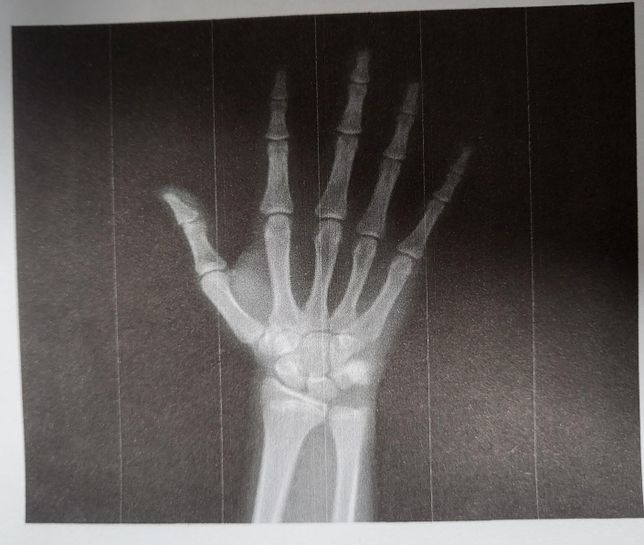

- 정형외과의료상담Q. 성장판 진짜로 닫힌걸까요...??몇일전에 정형외과가서 오른쪽 손목 성장판을 찍었는데 의사쌤이 뼈나이 17살이라고 이제 안큰다고 하셨는데...ㅠ 진짜로 닫힌걸까요..? 조금이라도 열려있는건 아닐까요..? 진짜 하나도 안클까요...?ㅠ 이제 예비 고1인데 키가 160.5 밖에안돼요...ㅠ 부모 유전키는 168.5인데..ㅠ 160후반대까지는 크고싶어요...ㅠ 가망이 없는걸까요...?6이미지가 포함된 질문이에요.

- 정형외과의료상담Q. 고1인데 키가 너무 작아요....ㅠ고1 남자고요 키는 160.5입니다 정형외과에가서 성장판 검사를했는데 손바닥을 엑스레이 찍었는데 손가락 마디 성장판은 거의다 닫혔고 손목만 조금 열려있다고 하셨어요 최종키는 161.6...이고요.. 근데 제가 중3 2월달부터 겨드랑이털이 나기 시작했거든요? 원래 겨털나고 2~3년동안은 키 크지않나요??? 160후반은 어려울까요?..?